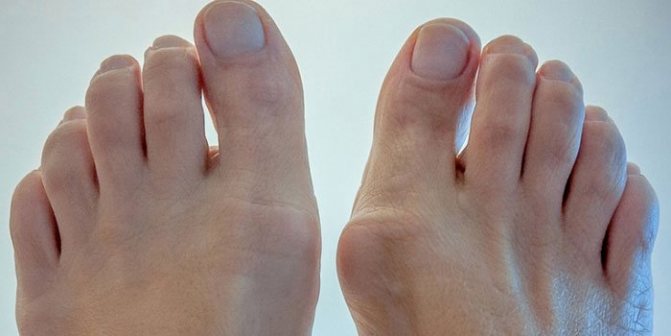

Следите за своими ногами, не дайте недугу развиваться

- На второй стадии остеоартроза характерно формирование «мягкого» образования в области деформации. Происходит нарушение функций синовиальной мембраны. Начинается развитие дистрофии суставной сумки и синовиальной мембраны. Костные разрастания — остеофиты — доставляют невыносимую боль. Появляется эрозия хрящевой оболочки сустава. Большой палец начинает отклоняться в сторону. Больной старается не наступать на него из-за болезненности, поэтому заметно косолапие. Возможно образование мозоли.

- Боли нарастают, сопровождая ежедневную деятельность. Развиваются характерные изменения первого плюснефалангового сустава: костные разрастания и бурсит в области головки 1 плюсневой кости и отклонение 1 пальца кнаружи (hallux valgus).Сложно подобрать обувь, присоединяется хромота. В этой стадии больные активно принимают обезболивающие препараты.

- Деформации обезображивающие, патологические изменения 1 плюснефалангового сустава нарастают, 1 палец смещается под второй, суставы которого тоже страдают. Имеются отеки и бурситы. Прогрессируют контрактуры и анкилозы, как пораженных остеартрозом, так и относительно интактных мелких суставов. Лекарства перестают помогать при болях. Страдает опороспособность.